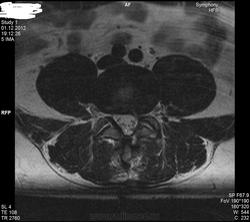

Уважаемые специалисты. МРТ после операции 8 нед.

Операция геминоламинэктомия L4-5 с установкой системы динамической стабилизации между остистыми 4-5.

После операции боли в пояснице прошли, боль в коленях и голенях осталась в неизменном виде. Ниже верхней трети голени боль не опускается.

По задней стороне туловища в ногах болей никогда не было. Уважаемый специалист, к сожалению не рентгенолог, утверждает что нет никаких признаков радикулопатии. Не посмотрите своим профессиональным взглядом.